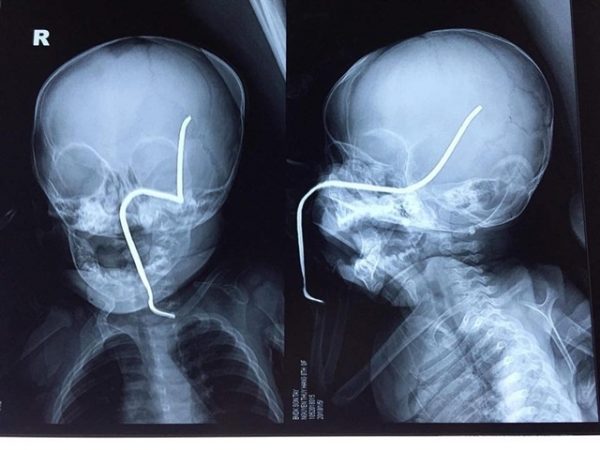

Hình ảnh phim X-quang của cháu H cho thấy thanh sắt đâm vào gò má trái, xuyên lên vùng não thái dương

Trong lúc được mẹ bế đi chơi gần nhà, cháu Nguyễn T.H (8 tháng tuổi, ở Sơn Tây, Hà Nội) không may bị một thanh sắt văng xuyên qua má, thủng hộp sọ của cháu. Theo người nhà bệnh nhi, nguyên nhân của tai nạn thương tâm này là do chiếc máy cắt cỏ đang hoạt động cách đó 15m bất ngờ làm bắn văng một thanh sắt rỉ nằm ẩn dưới cỏ trúng vào cháu bé.

Các bác sĩ khoa Cấp cứu – Chống độc (BV Nhi Trung ương) cho biết, cháu H vào viện chiều ngày 1.5 trong tình trạng vật vã, quấy khóc, có dị vật là thanh sắt đâm xuyên thẳng vào má trái. Cháu được truyền kháng sinh, giảm đau và tiêm phòng uốn ván, đồng thời làm các xét nghiệm cần thiết. Sau khi hội chẩn, ngay trong đêm 1.5, bệnh nhi được tiến hành phẫu thuật rút dị vật ra.

Theo Ths.Bs Hồ Trung Luân, khoa Ngoại Thần kinh, người trực tiếp phẫu thuật cho bệnh nhi, ca mổ khá khó khăn do thanh sắt cũ, giòn nên rất dễ gãy, lại đâm qua gò má trái, đâm thủng sàn sọ, xuyên qua vùng não thái dương và vùng đỉnh sát các mạch máu lớn nên nguy cơ chảy máu trong khi mổ là rất lớn, đồng thời nguy cơ nhiễm trùng não.Tuy nhiên, sau hơn 30 phút phẫu thuật, dị vật đã được gắp ra an toàn. Hiện trẻ đang được tiếp tục theo dõi sau mổ, kiểm soát tình trạng phù não, chống nhiễm trùng, chảy máu tại khoa Hồi sức ngoại.